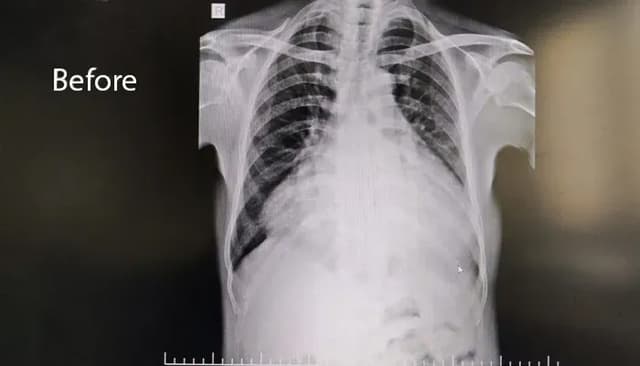

Diagnostic Imaging & Early Diagnosis

Advanced cardiac imaging and detailed diagnostic evaluation enabled:

- Clear identification of the rupture

- Precise surgical planning

- Reduced intraoperative risk